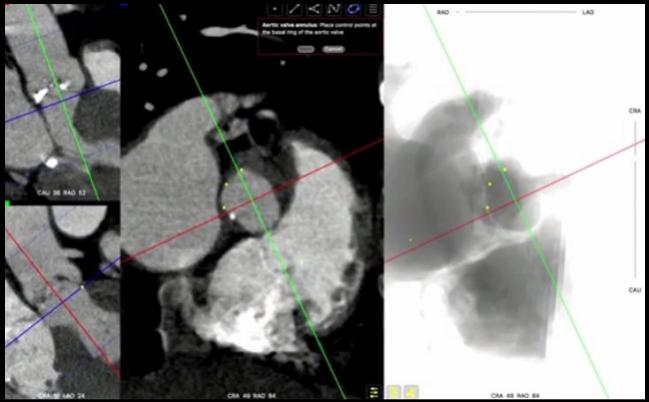

Photo Credit: Captured from TVT 2016: Live Case #13: TAVR. McGill University Health Center, Royal Victoria Hospital, Montreal, Quebec. June 17, 2016.